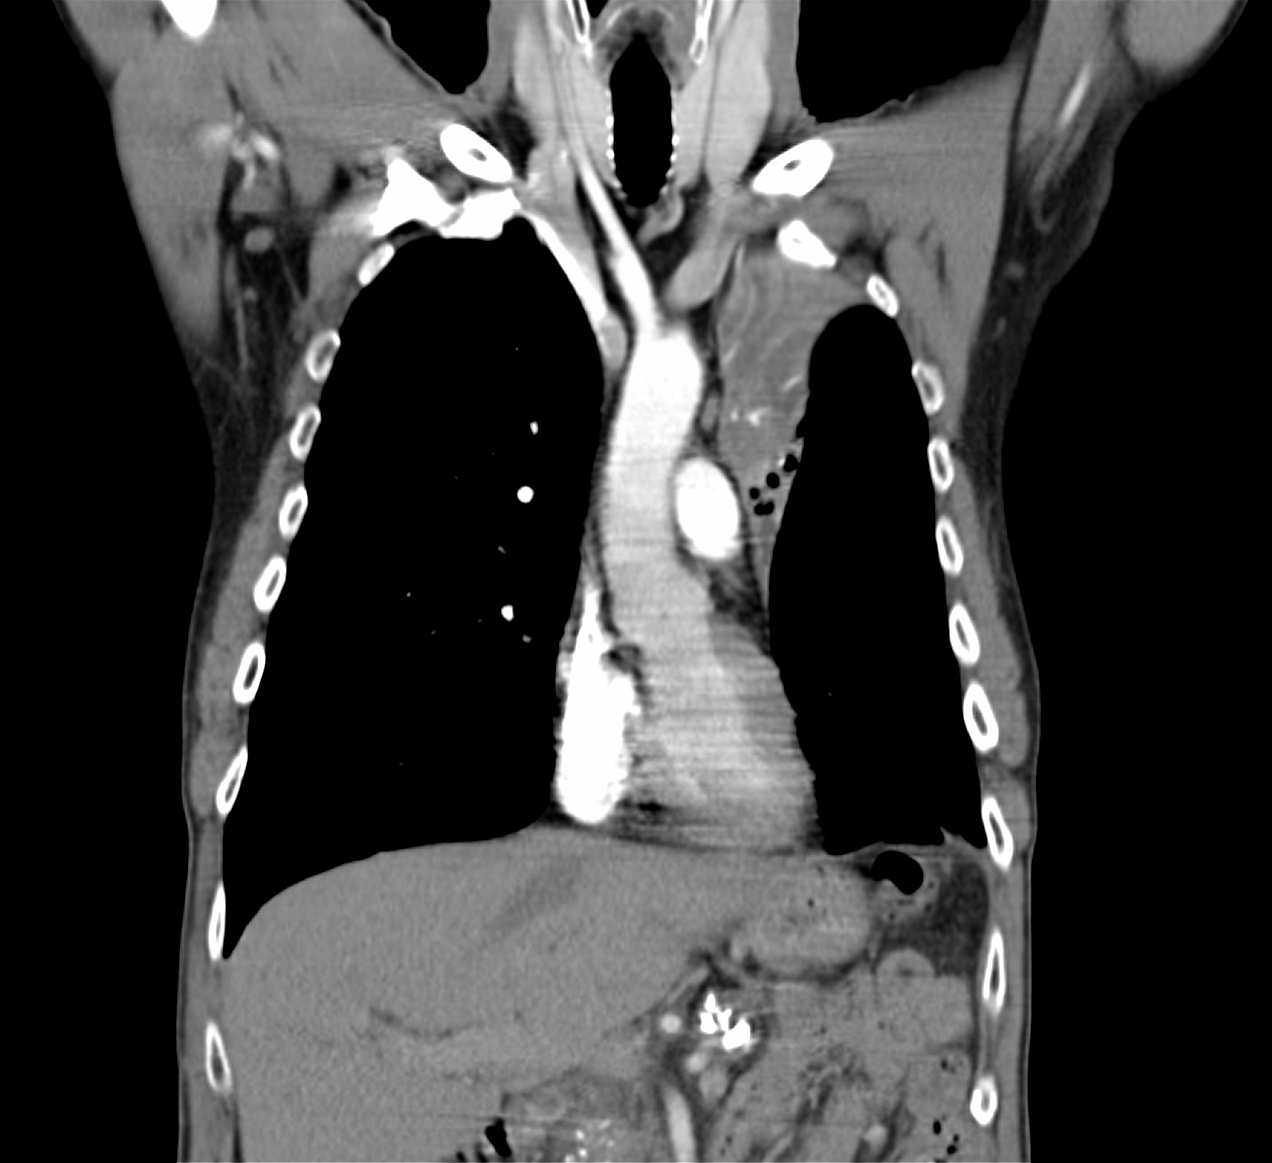

21. Left sided peripheral lung tumor

22. Central lung tumor with mediastinal lymphadenopathy. CT coronal and sagittal reconstructions.

70 year old man, COPD, hoarse. Right hilar mass, bronchoscopy was negative.

The larynx is rotated to the right, no motion of the right side of the larynx can be observed, swollen left plica ventricularis area.

CT: 13x11 mm large nodular mass in the left 10th segment. Bilateral hilar lymphadenomegaly with central hypodensity. A 34x21 mm large lymph node conglomeration can be observed in subcarinal location (peripheral contrast enhancement). Lymphadenopathy in the aortopulmonary window (15 mm large), and a 26 mm large lymph node can be observed in paraaortic location above the trachea bifurcation which has an esophagus-compressing effect. In the superior chest aperture there is a 38x28 large fused lymph node conglomerate which causes the left shift of the esophagus and trachea.